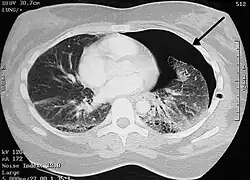

Badanie TK

Badanie TK klatki piersiowej pozwala na dokładniejszą ocenę odmy opłucnowej niż zdjęcia RTG, ale jej zastosowanie w tym wskazaniu nie jest rutynowo zalecane. Tomografia komputerowa klatki piersiowej może być przydatnym badaniem w wybranych przypadkach. Pozwala między innymi rozróżnić pęcherze rozedmowe od odmy opłucnowej w sytuacji, gdy obraz RTG jest niejednoznaczny. W sytuacjach pourazowych, gdy uzyskanie zdjęć w pozycji stojącej może być niemożliwe, w około jednej trzeciej przypadków odma opłucnowa może nie być widoczna na zdjęciach rentgenowskich, podczas gdy badanie tomografii komputerowej zachowuje wysoką czułość. Dodatkowo tomografia komputerowa może być przydatna w rozpoznaniu chorób, które doprowadziły do powstania odmy opłucnowej.